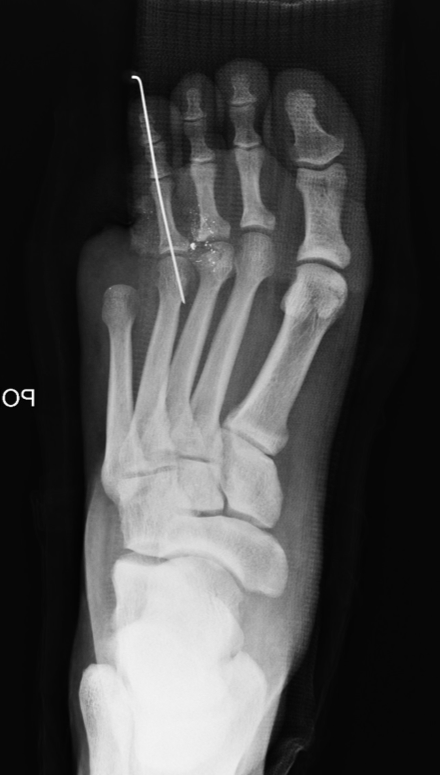

His pre-op X-rays indicated multiple bullet fragments along with severely comminuted middle and distal phalanx fractures of the fifth toe with bone loss (see right photo). The patient also had a fourth digit dislocation at the metatarsophalangeal joint.

With consideration of the long-term morbidity associated with the injury, we performed a primary fifth toe amputation (see left photo). We also performed open reduction of the fourth toe dislocation and stabilized the toe with a K-wire. After removing the bullet fragments, we noted a non-displaced third metatarsal head fracture radiographically and addressed this with non-surgical treatment.